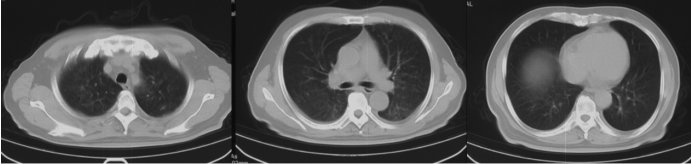

复查胸部CT:双肺支气管血管束增粗,见多发结节影、斑片影及磨玻璃密度影。双肺见索条影;肺门、纵隔未见肿大淋巴结;双侧少量胸腔积液。心包少量积液(图2)

图2  外院胸部CT(2023-04-07)

图5  患者胸部CT变化

复查胸部CT,与前期相比,患者双肺病变逐渐吸收(图9)

图9  复查胸部CT